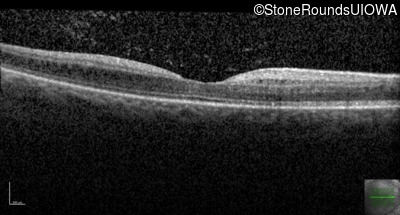

Age at visit: 18 years